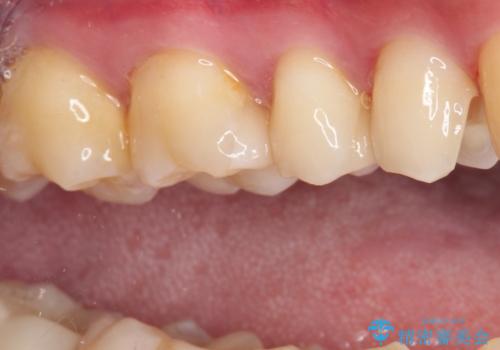

詰め物が外れた セラミックインレー修復

- 以前治療した詰め物が外れてしまい、冷たいものがしみることを主訴として来院された患者様です。

むし歯がないことを確認し、セラミックインレーにて修復するととしました。

適合の良いセラミックインレーの装着により、冷たいものがしみる症状はなくなりました。